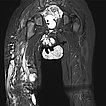

Coronal T2-weighted, fat-suppressed MRI of the pelvis and thighs shows the large extension of the malformation. Multiple sections with microcystic and macrocystic lymphatic malformation components. In addition, an extensive venous malformation with a large marginal vein laterally on the right thigh.